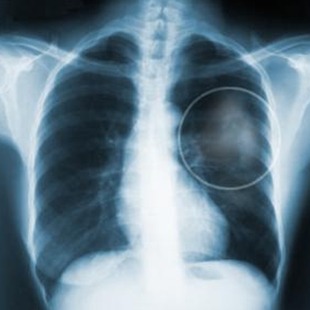

폐암말기증상에 대해 알고 계십니까? 폐암이라는 병은 알고 있어도 어떠한 증세가 나타나는지 알고 있는 분은 의외로 많지 않습니다. 폐암은 사망위험이 높은 무서운 질병으로 초기에는 무증상이지만 진행 되면 다양한 자각증상이 나타나게 됩니다. 따라서 미리 폐암말기증상과 초기증상에 대해 알아두고 예방할 수 있도록 하는 것이 필요합니다.

앞서 소개해드린 것처럼 폐암 초기증상은 거의 없는 편이며 진행이 되고 전이가 된 폐암말기증상은 다른 암보다도 괴롭고 고통스럽다고 합니다. 어떤 암이라도 말기에는 상당한 고통이 수반되는데 폐암말기의 경우 호흡곤란, 각종 통증으로 인해 진통제를 투여하지 않으면 견딜 수가 없을 정도입니다.

다른 암과 비교해도 폐암의 말기증상이 고통스럽기 때문에 폐암 초기증상이 의심될 경우 서둘러 치료를 받아보는 것이 좋습니다. 하지만 초기증상인 기침이나 가래는 심하지 않아서 무시하고 넘기는 분들이 많다고 합니다.

만약 아래 증상이 있을 경우 폐암말기증상으로 진행되기 전인 초기~ 중기 증세이니 해당하는 항목이 많은 분들은 검진을 받아볼 수 있었으면 합니다.